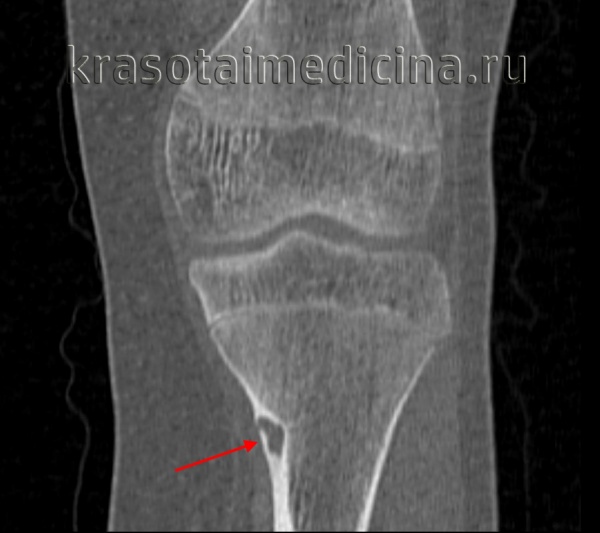

(Слева) На корональной КТ в костном окне в верхнечелюстной пазухе, решетчатом лабиринте и полости носа справа определяется огромная остеома смешанной плотности. Дно глазницы истончено. Носовые раковины справа не визуализируются. Края оаеомы повторяют границы анатомических аруктур, но не приводят к их вздутию.

(Справа) На сагиттальной КТ (реконструкция) в задних отделах правой верхнечелюстной пазухи определяется большая компактная остеома с бугристыми краями, распространяющаяся кверху в задние отделы глазницы и приводящая к проптозу у этого пациента. (Слева) На аксиальной КТ без КУ у пациента с синдромом Гарднера в правой верхнечелюаной пазухе определяется маленькая кортикальная остеома на ножке. Признаки синусита отсутавуют. В области ветви нижней челюсти с обеих сторон видны большие остеомы.